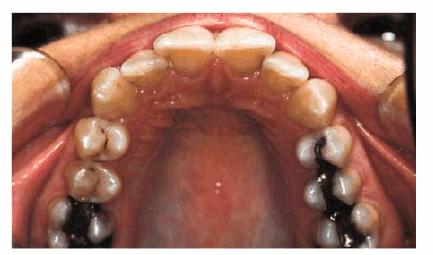

PROBLEM: This 38-year-old store owner presented with crowded and

discolored maxillary and mandibular teeth (Figures 24-7A, and 24-7B). Although orthodontic treatment was suggested as ideal

treatment, he elected a compromise that consisted of bonding the mandibular and

Figure 24-7A: This 38-year-old man wanted to improve his crowded maxillary and mandibular teeth.

Figure 24-7B: This occlusal view shows why full orthodontic treatment was originally presented as the ideal treatment. The patient insisted on a "quick fix" solution.